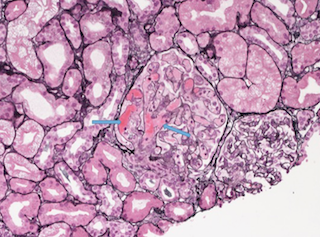

Renal biopsy was done